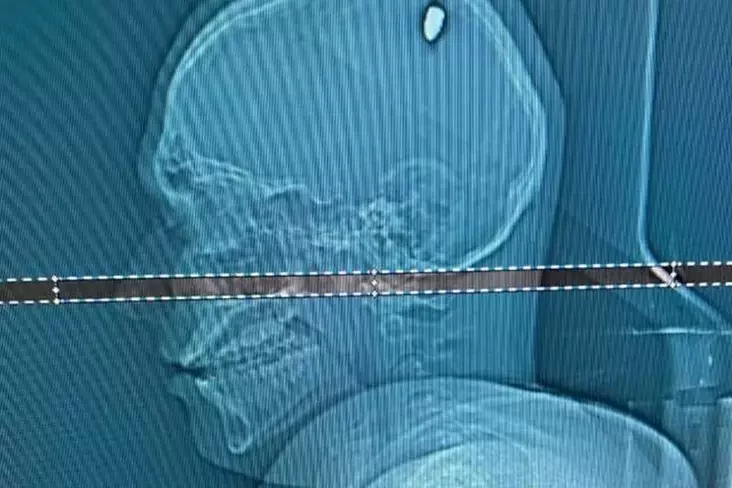

После сна левая рука Матеуса заметно ослабла — он не мог поднять даже легкие вещи. Парень обратился к врачу, и ему сделали МРТ. На томографии выяснилось, что источником проблемы была пуля, застрявшая в одной из некритических частей мозга. Ее извлекли хирургическим путем.